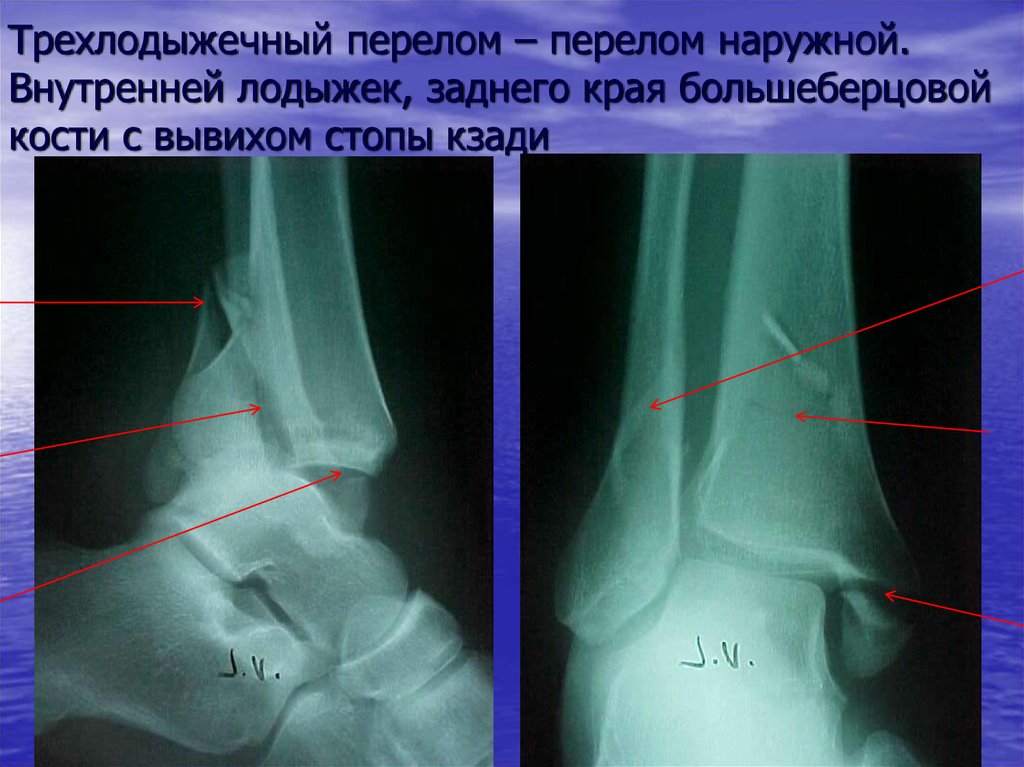

- Trimalleolar Fracture: Affects all three malleoli (lateral, medial, and posterior)